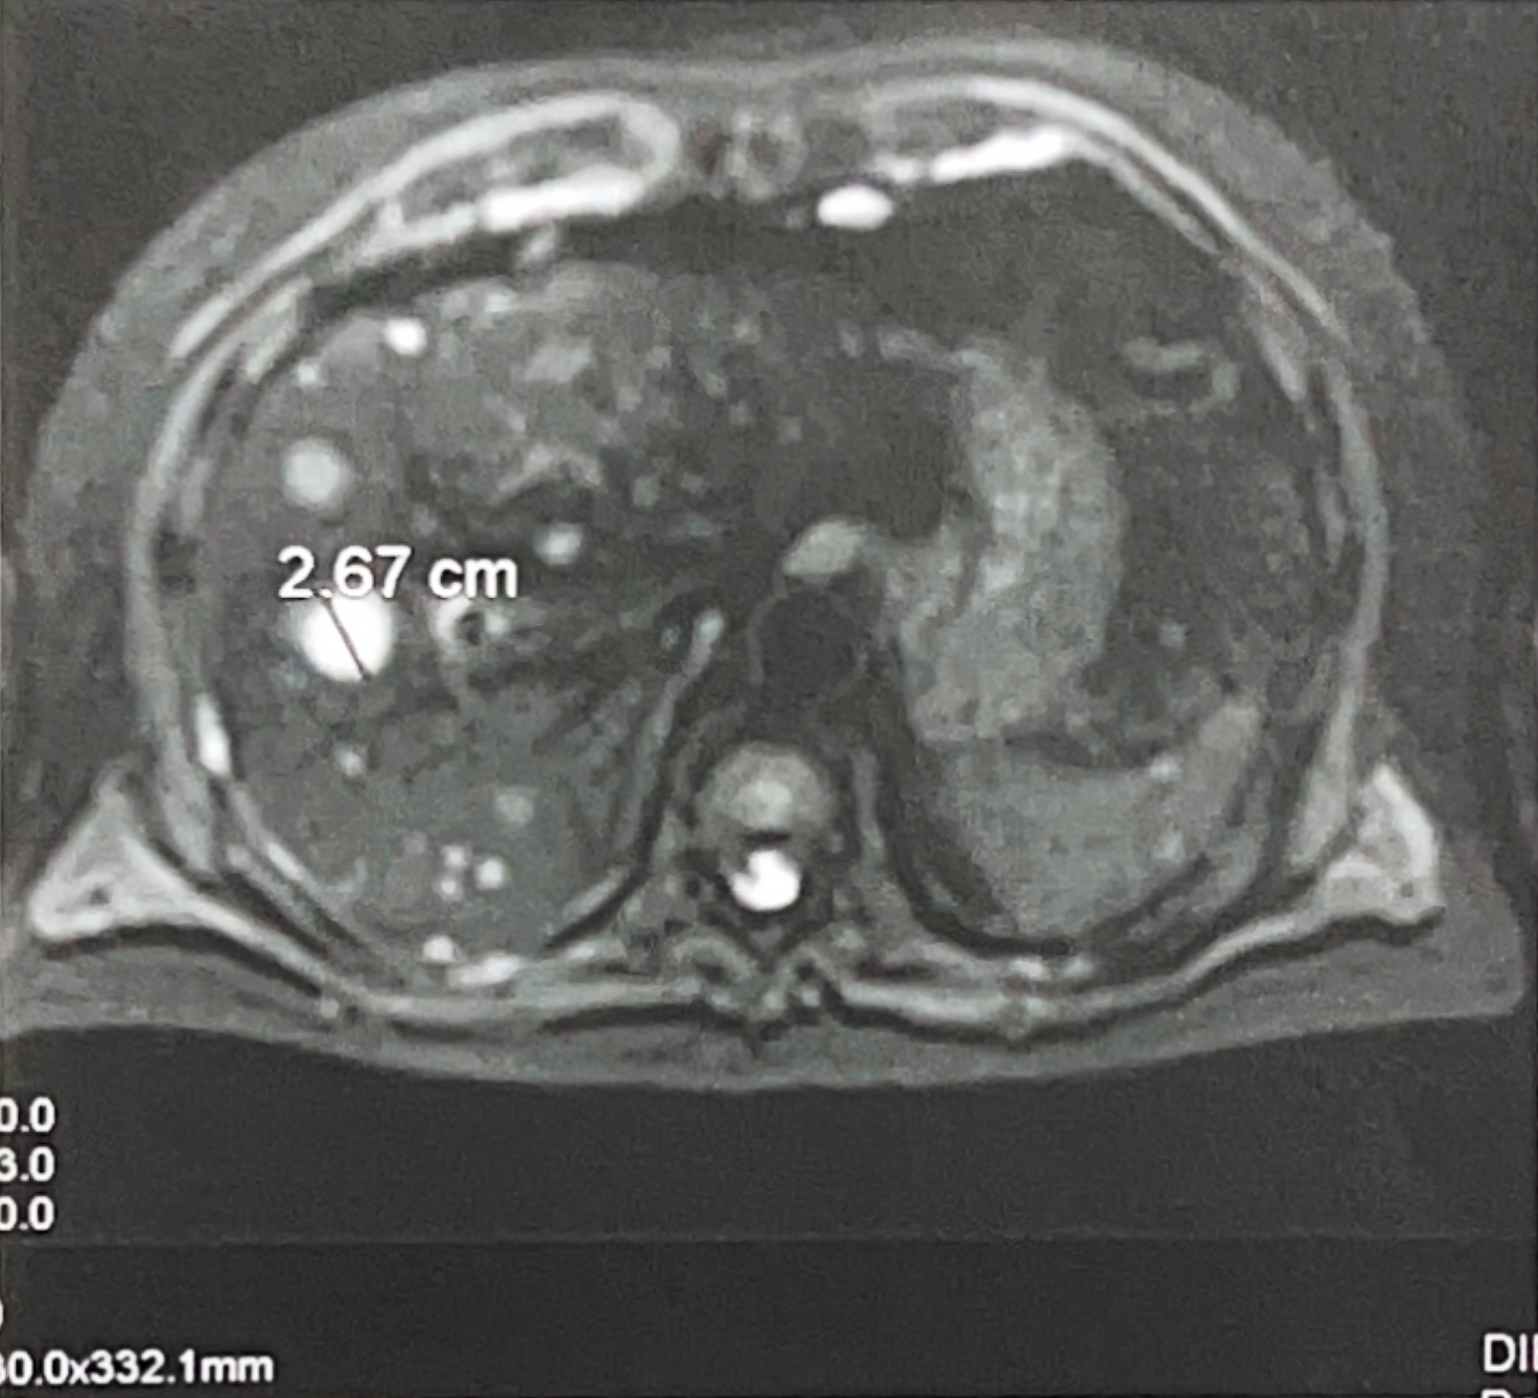

Liver MRI Scan Showing Liver Metastatic Tumor (Scan Before The Procedure)As part of ongoing monitoring, the patient underwent a PET-CT scan. The results showed metastatic changes in the liver, including a lesion measuring 26 mm. The scan also identified several enlarged lymph nodes along the left iliac vessels.

The pattern suggested progression and raised an important question. Was this still behaving like a typical prostate adenocarcinoma, or had the biology shifted?